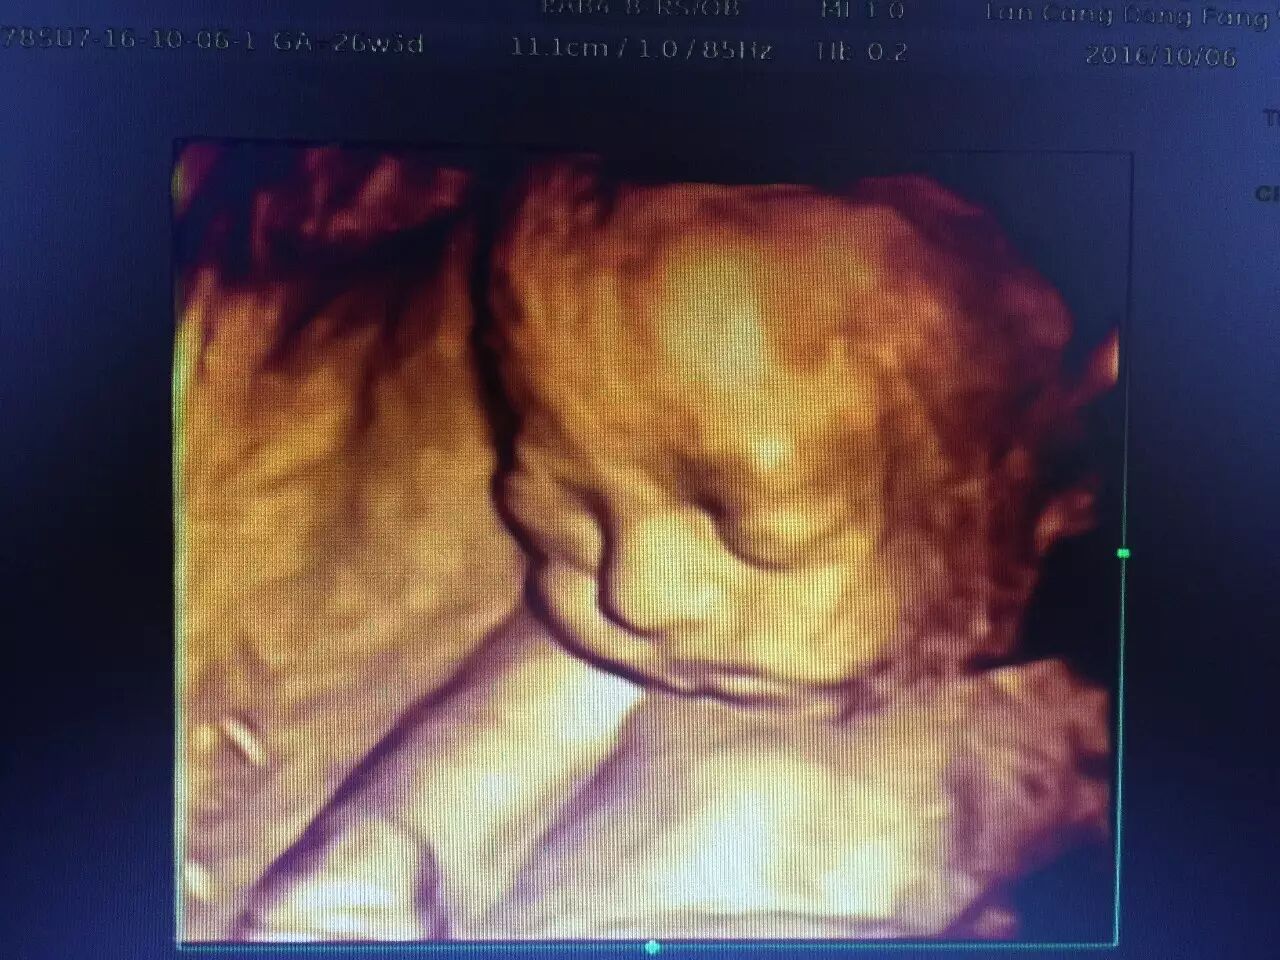

我院引进了美国GE公司的四维彩色超声诊断仪,四维彩超的全称为四维彩色超声诊断仪,是世界上最先进的彩色超声设备。

其结果是:这种高科技设备能够显示你未出生的宝宝的即时动态活动图像,或者人体内脏器官的即时活动图像。

与 3D超声波成像系统相比,四维彩色B超可以使得医生即时地观察胎儿在子宫内的动态运动,判断胎儿的发育情况。

其优点一改既往二维超声中黑白色调的静态平面图像,而变成有色彩的立体动态的人体器官(包括胎儿)的实时活动图像,使医生的诊断更精确、可靠

排查胎儿发育是否畸形,可以清楚的看到孩子的发育情况,除了能看到孩子的五官发育,四肢发育以外,内部心脏,肾脏发育,脊柱发育,脑部发育四维彩超也能清楚的看到。